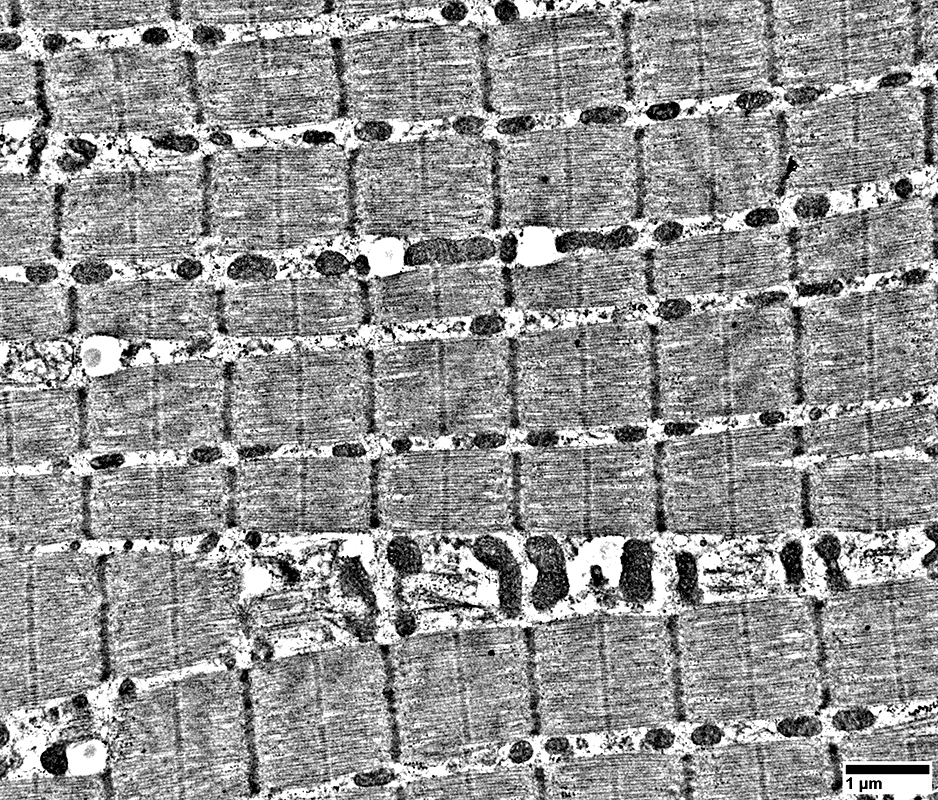

Muscle mitochondria with normal structure.

From: R Schmidt

Mitochondria

Numbers: Increased

Localization: Either side of Z-line